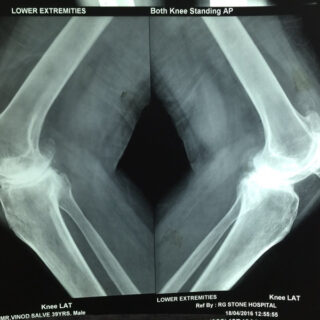

Youngest Patient 39 years old Bilateral Total Knee Replacement done in one sitting.

X-rays of patient of bilateral knee replacement in one sitting before and after surgery